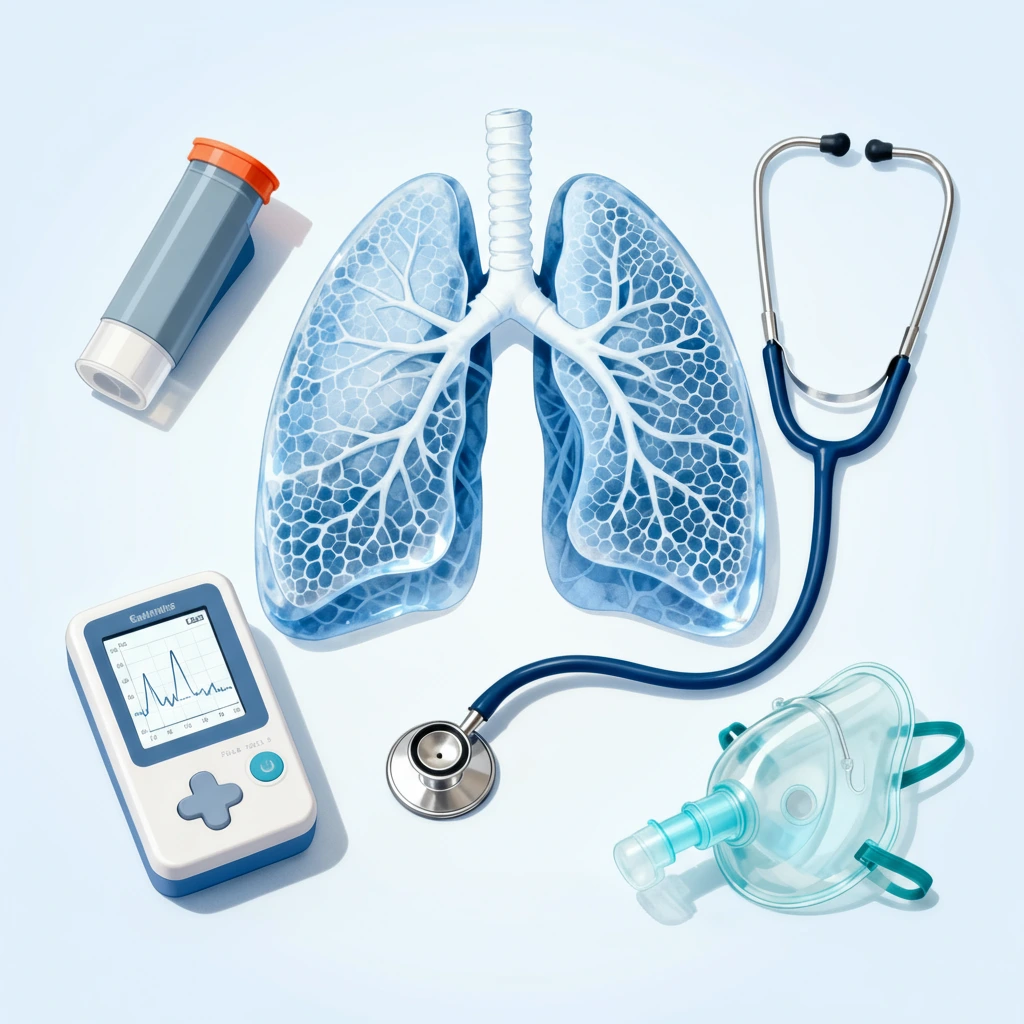

Get expert care for all your lung and breathing related problems from Dr. Satyajit Acharya, a trusted pulmonologist with over 15 years of experience. With our dedication to improving respiratory health, we are here to help you breathe better and live a healthier life right in Bhubaneswar

We specialize in complete care for various lung and breathing conditions. Here is a clear overview of our expertise, so it is easy for you to find what you need:

You will find full support for managing asthma, helping you control symptoms and breathe more easily every day from the best chest specialist near you. Our asthma clinic near you specializes in various chest-related conditions and provides you with expert diagnosis and best treatment for respiratory care so you recover fast.

We have advanced care for Interstitial Lung Disease (ILD), which means you will get the best treatment for ILD, from lung scarring to providing precise diagnosis and management to protect your lung function. The lung specialist in our clinic utilises the latest methods for advanced lung testing to obtain a clear picture of your lung health, thereby guiding the most effective treatment.

We perform advance pulmonary function testing at our advance pulmonary care centre to measure how well your lungs are working, helping us understand your breathing capacity and identify issues. Our clinic also offers specialized TB care where TB specialists through complete diagnosis and treatment for tuberculosis focus on your full recovery.